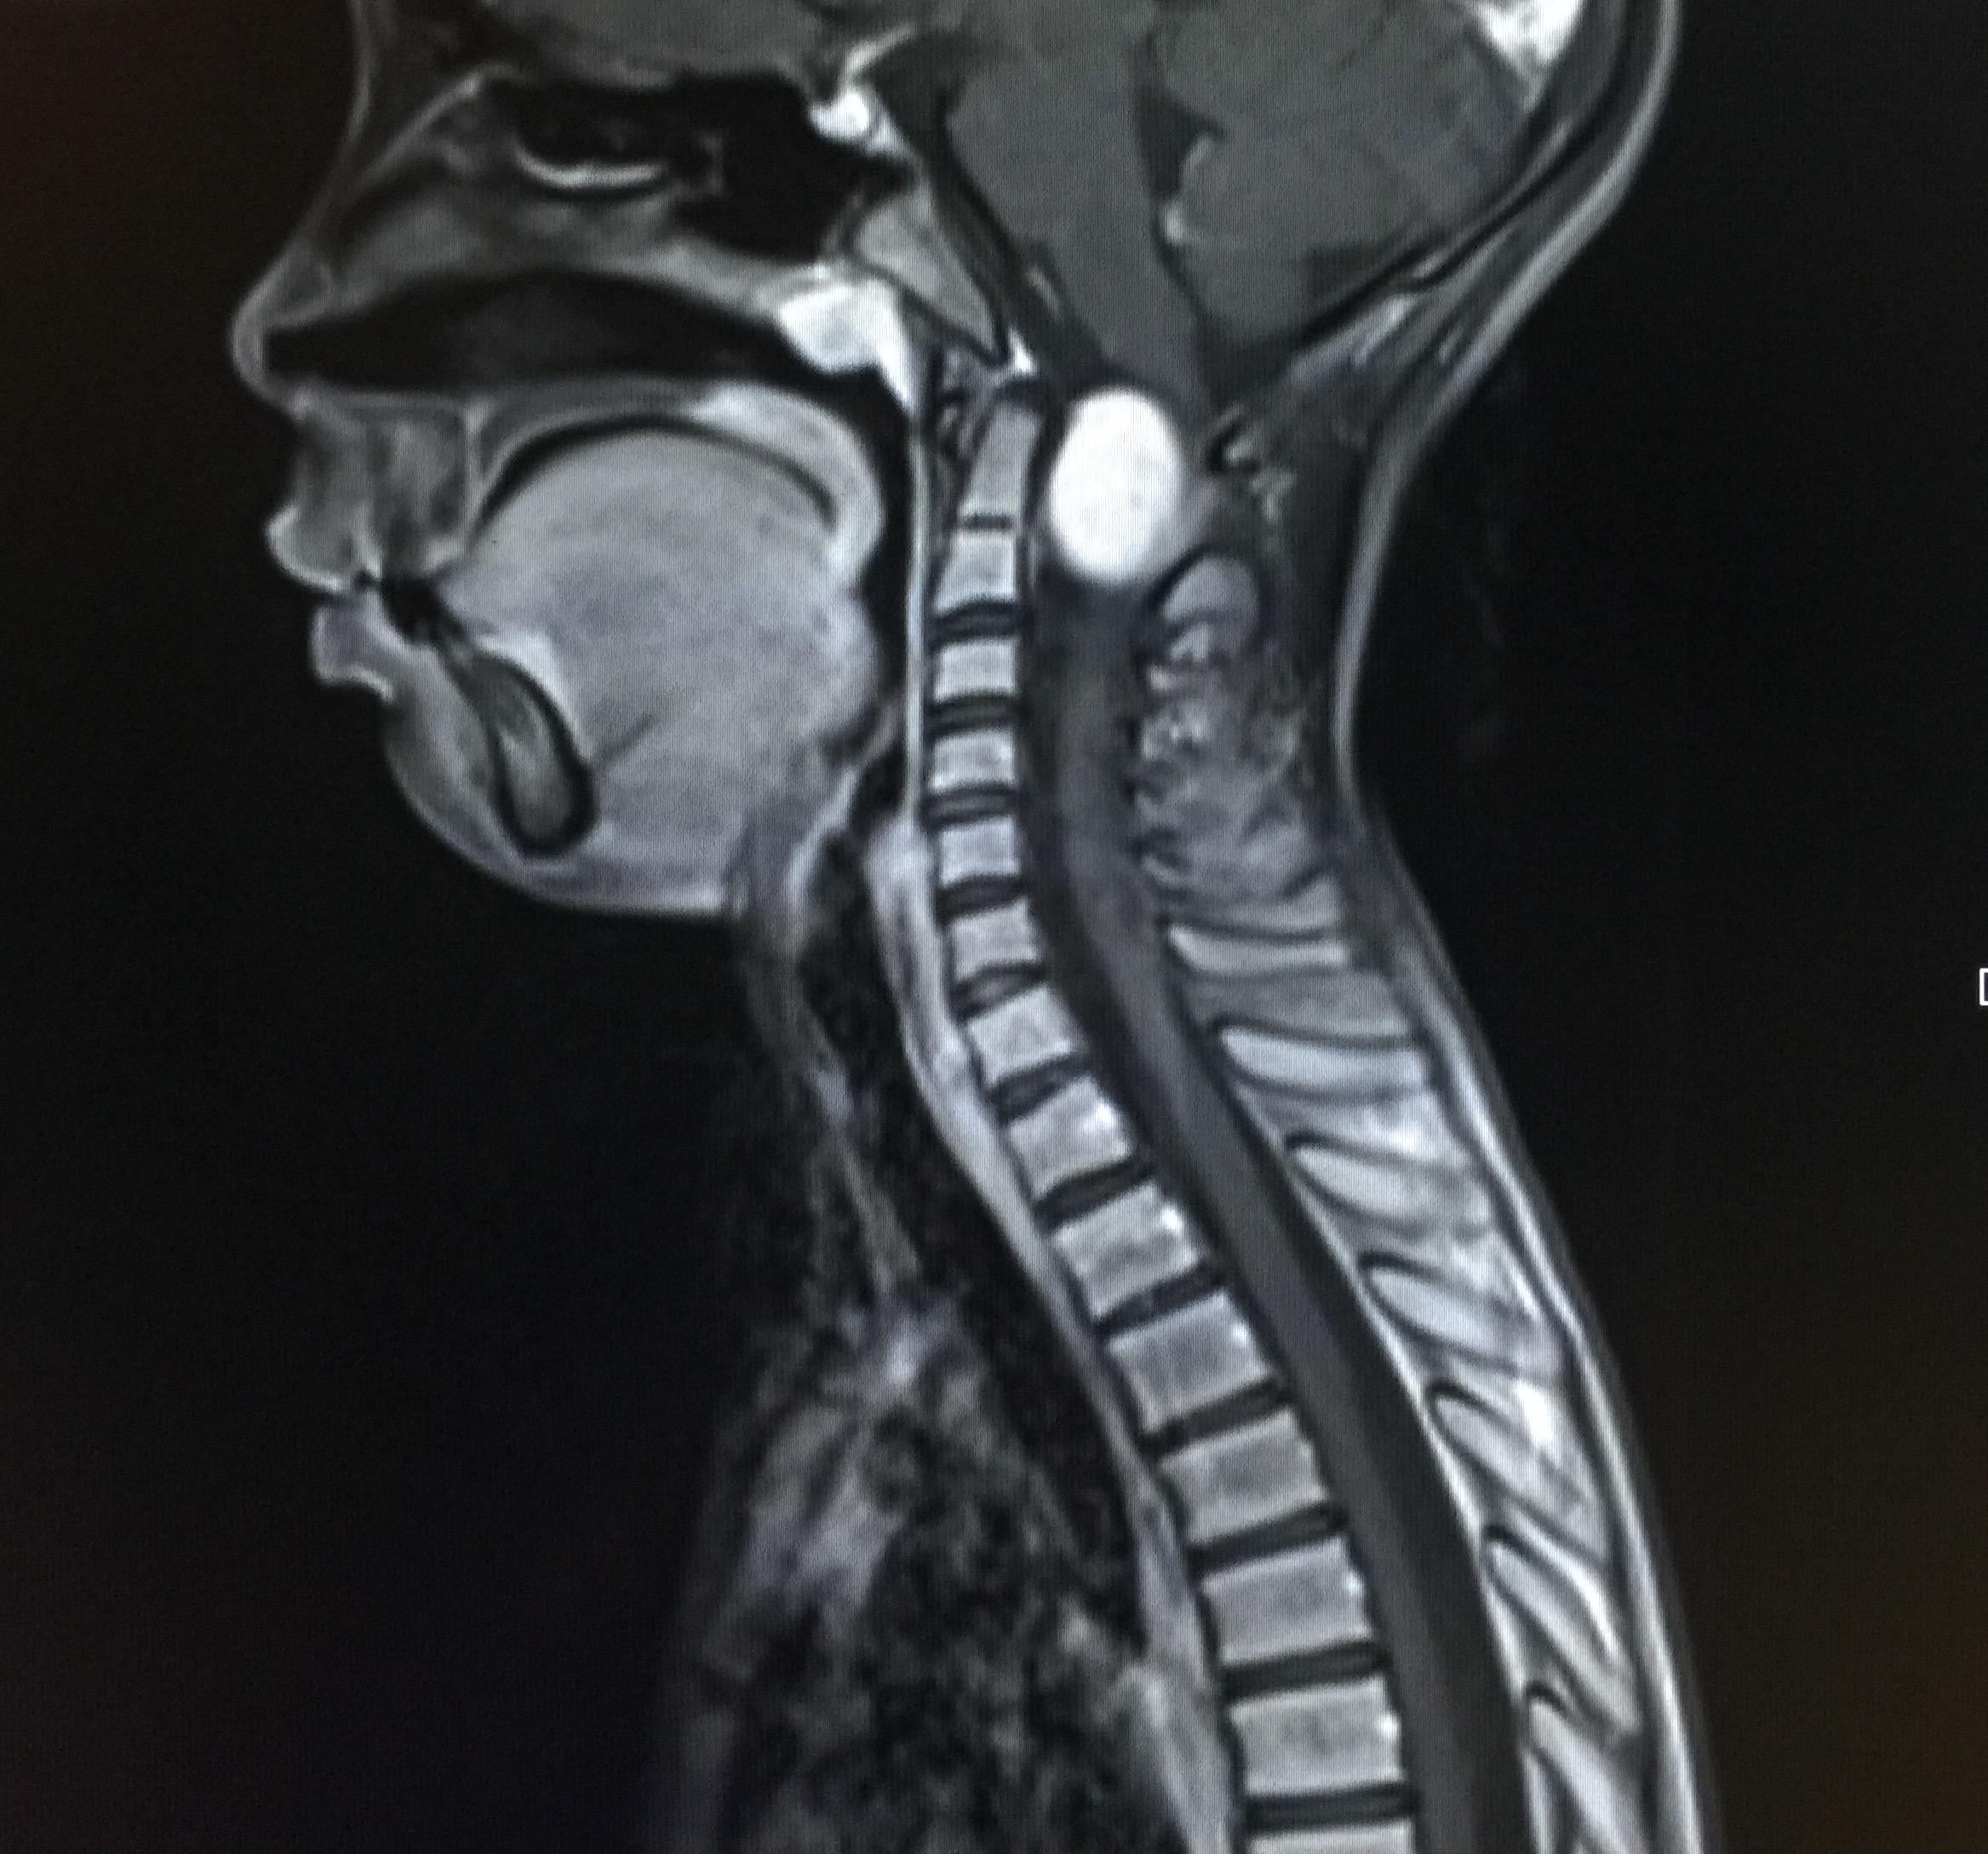

頭顱位置的神經鞘腫瘤通常發生在大腦內的神經,當中以聽覺神經、三叉神經及迷走神經的發生率較高,發生在交感神經的腫瘤則最為少見。這類腫瘤的患者多為中年人士,男女患病情況相若,磁力共振檢查會看到腫瘤呈圓形或卵形,若腫瘤體積較大則可能有液化情況,影像猶如囊腫一般。